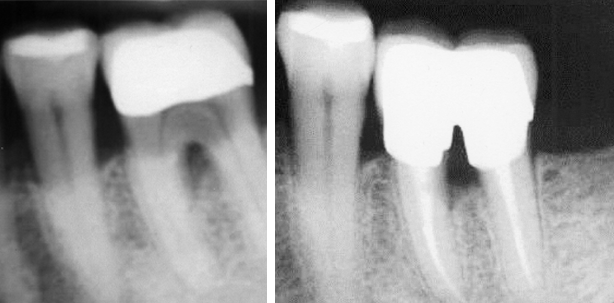

Fünf Tage nach der Erstvorstellung wurde die Behandlung in einer Sitzung vorgenommen. Die Durchtrennung des Zahnes erfolgte gleich zu Beginn, um die Erhaltungsfähigkeit und -würdigkeit beider Wurzeln beurteilen zu können und abzuschätzen, ob deren Erhalt möglich und sinnvoll war. Danach wurde jede Wurzel einzeln unter Kofferdam vollständig aufbereitet. Beide Wurzeln enthielten jeweils zwei Kanäle, die mit #35/6°-GP gefüllt wurden (adhäsive WF). Zeitgleich mit dem adhäsiven Aufbau wurden in jeden vestibulären Kanaleingang Glasfaserstifte eingebracht. Abschließend wurde eine chairside gefertigte provisorische Krone mit TempBond eingegliedert (Zinnhülse mit Provisoriumskunststoff unterfüttert, interradikulär durchspülbar gestaltet).

Acht Monate später zeigte die Röntgen-Kontrollaufnahme gesunde apikale Verhältnisse sowie keine Anzeichen von zusätzlichem Knochenabbau. Die Präparation für eine Krone gestaltete sich aufgrund der kaum entzündeten marginalen Gingiva (Durchspülbarkeit des Provisoriums und sehr gute mundhygienische Mitarbeit des Patienten) komplikationslos, eine leichte Hohlkehle konnte angelegt werden.